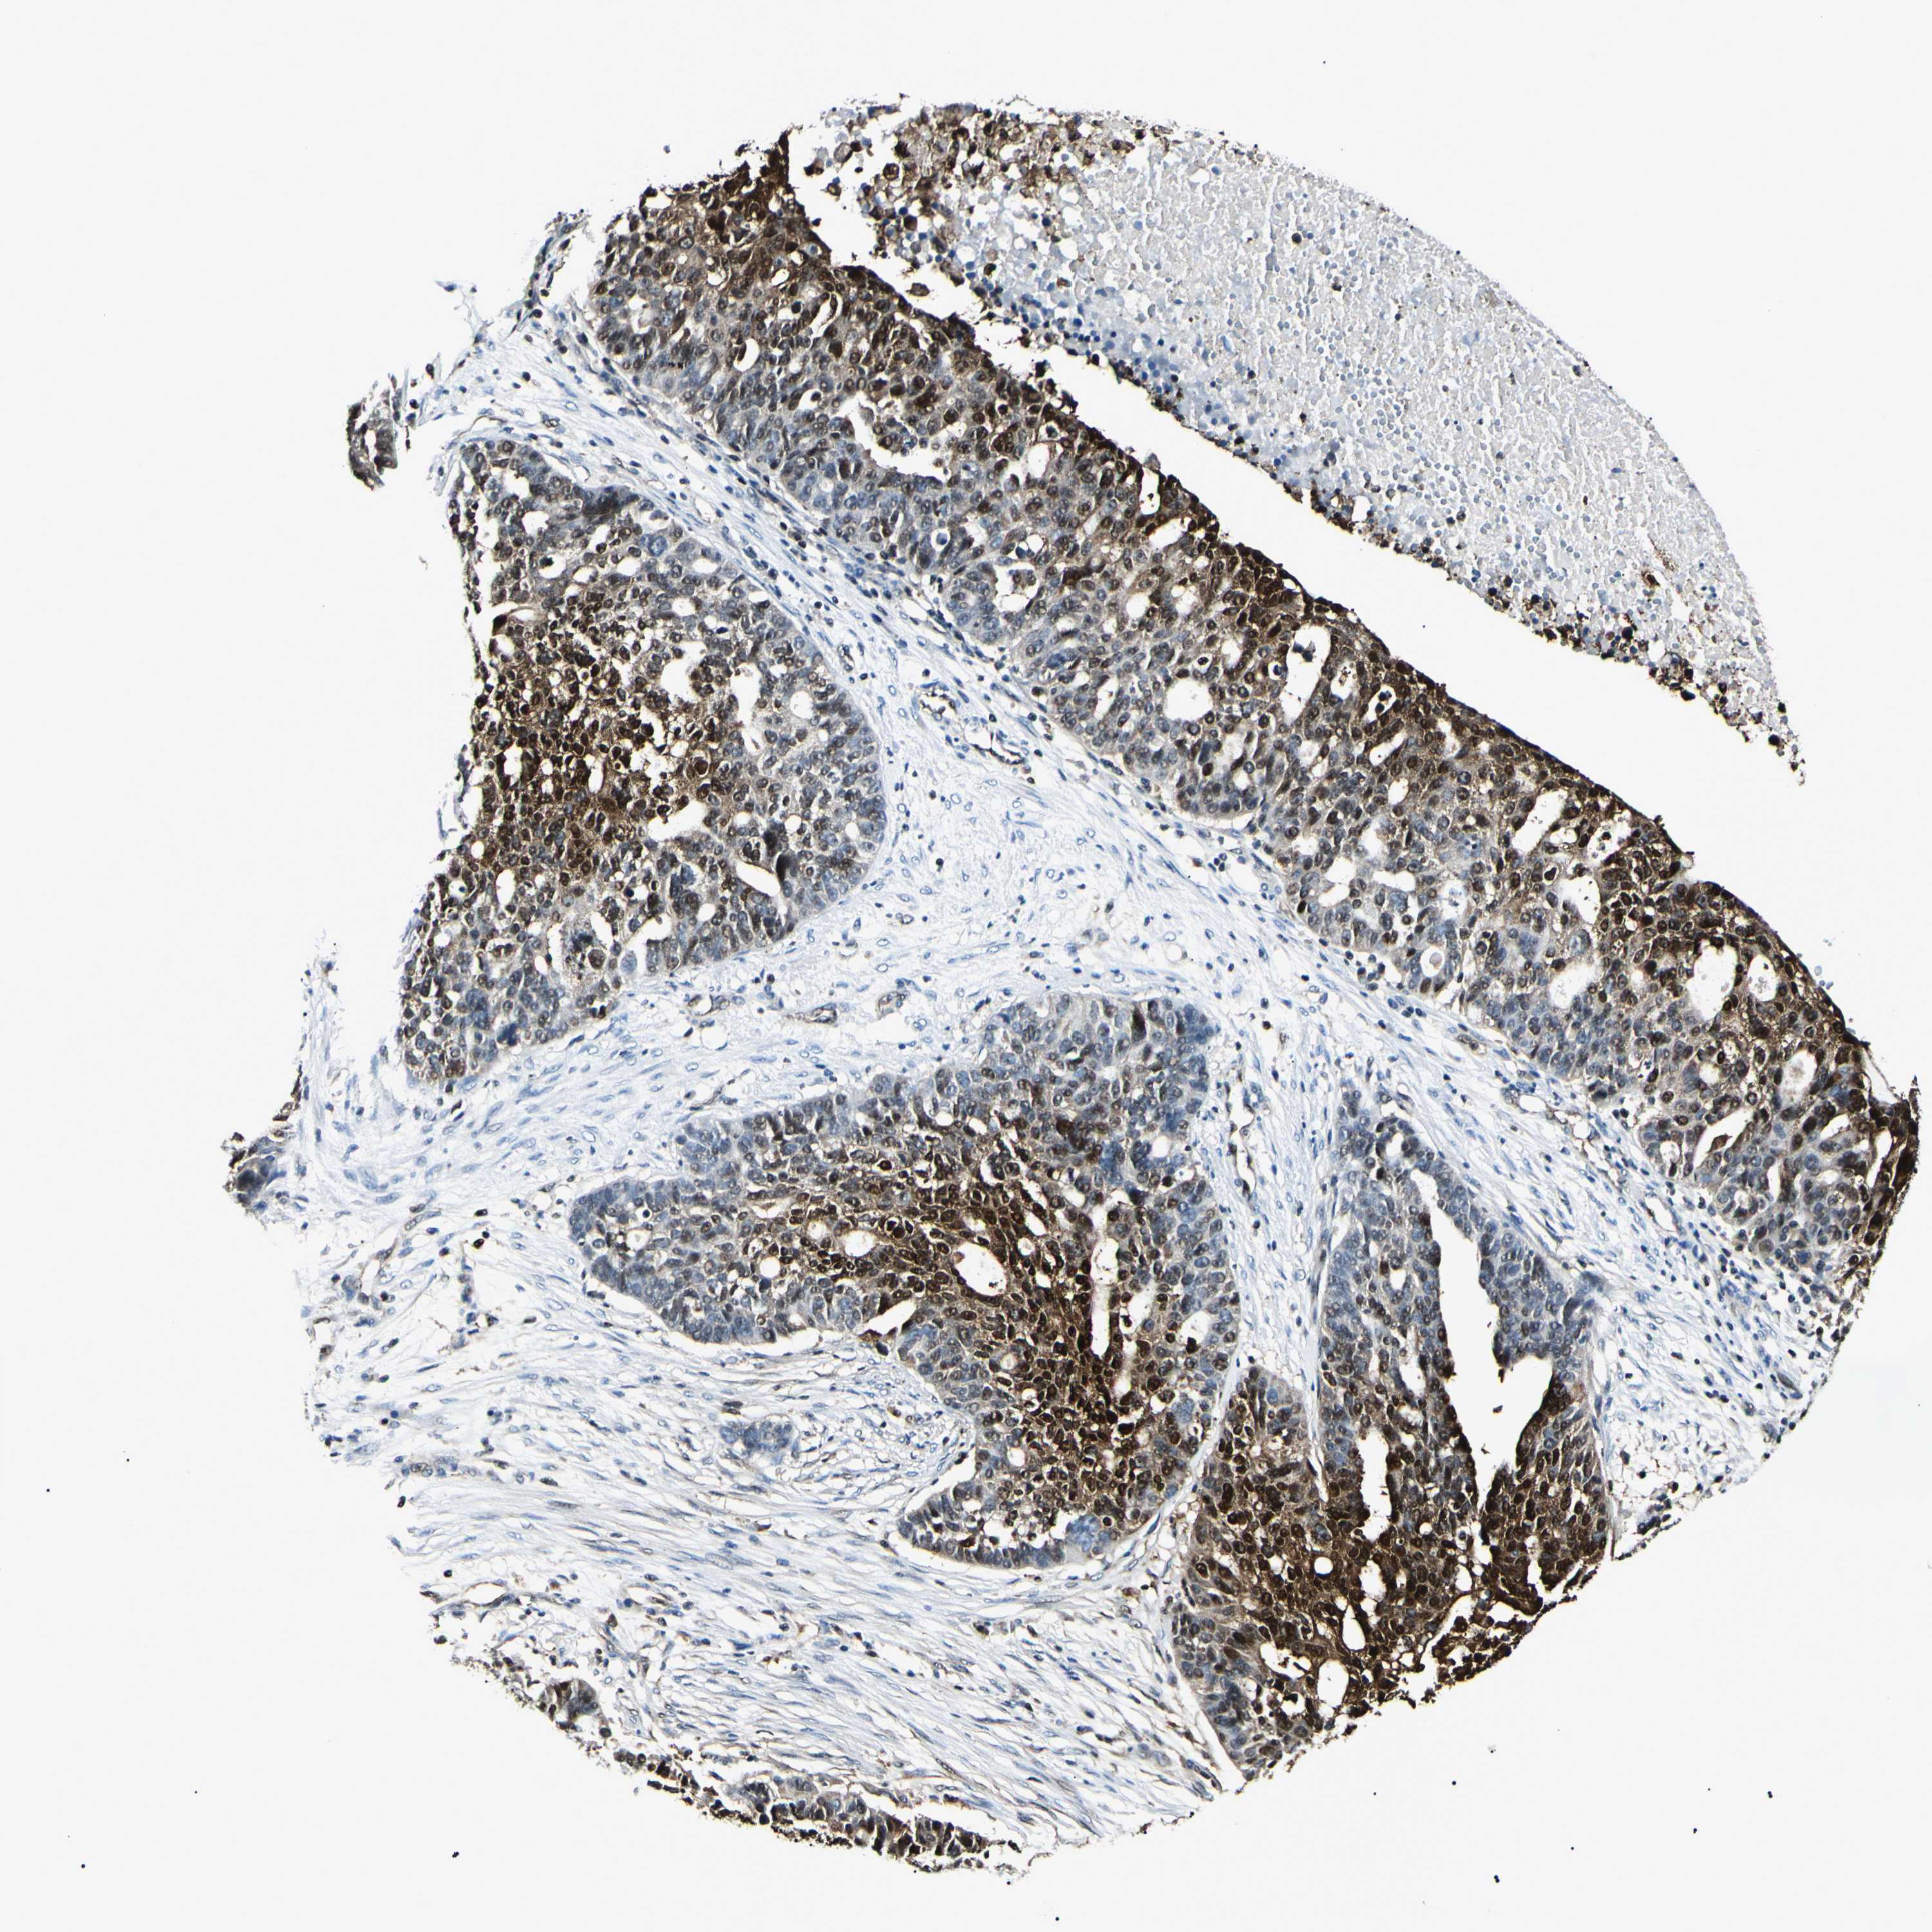

OVARIAN CANCER - Protein expressioni

A mouse-over function shows sample information and annotation data. Click on an image to view it in a full screen mode. Samples can be filtered based on level of antibody staining by selecting one or several of the following categories: high, medium, low and not detected. The assay and annotation is described here.

Note that samples used for immunohistochemistry by the Human Protein Atlas do not correspond to samples in the TCGA dataset.

Antibody stainingi

Antibody staining in the annotated cell types in the current human tissue is reported as not detected, low, medium, or high, based on conventional immunohistochemistry profiling in selected tissues. This score is based on the combination of the staining intensity and fraction of stained cells.

Each image is clickable and will lead to virtual microscopy that enables deeper exploration of all samples and also displays staining intensity scores, fraction scores and subcellular localization as well as patient and tissue information for each sample.

Antibody HPA045385

Antibody CAB010065

Staining

High

Medium

Low

Not detected

Cystadenocarcinoma, serous, NOS